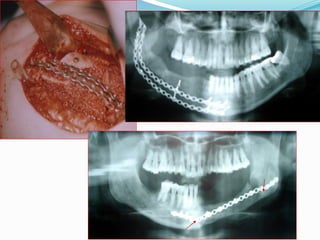

Solid or Multicystic Ameloblastoma:

Treatment

•General Principles:

 Treatments have ranged from

simple enucleation and

curettage to en bloc resection.

behavior & Histologic assessment.

 Marginal resection is the most

•" The Goal is Total Removal (? Pt Med Status).

widely used method of

•" Curettage & Enucleation should be

treatment with the least

recurrences reported (up to 15

Abandoned ?! Curettage can disperse tumor

%).

cells into uninvolved areas.

•Microscopic Infiltration of Bone beyond the  Most surgeons advocate a

margin of at least 1.0 cm

Image Margin.

beyond the radiographic limits

•" Safety Margin must be employed as follows:

of the tumor as the tumor often

extends beyond the apparent

•2 cm for Solid & Multicystic 1-1.5 cm for

radiologic/clinical margins.

Unicystic & Peripheral.

•" Treatment must be Guided by Biologic

•" Post Treatment F Up for 15-20 Yrs.

The treatment of the classic infiltrative, more aggressive

ameloblastoma should not be taken lightly. Mandibular resection must

include an adequate zone of normal-appearing bone around the main

tumor mass. Extension of tumor into surrounding soft tissues is an

ominous sign and demands surgery in these areas as vigorous as within

the confines of the bone.

 Maxillary ameloblastomas require more aggressive initial management

with at least a 1.5 cm margin of radiographically normal bone.

Postoperative follow-up is critical for a minimum of 10-15 years.